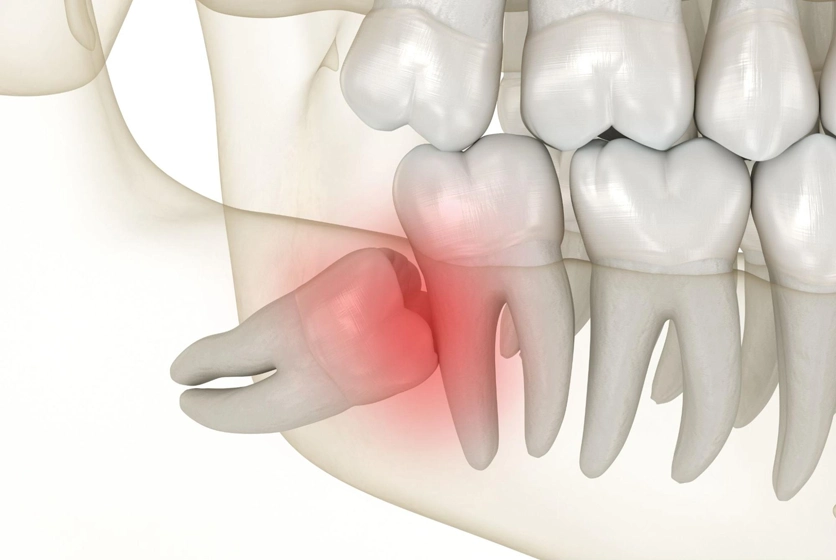

Weisheitszähne bereiten vielen Patienten Probleme: Sie brechen schief durch, verdrängen andere Zähne oder verursachen Entzündungen. Auch wenn genug Platz vorhanden ist, können sie langfristig die Kiefergesundheit beeinträchtigen. In unserer Praxis in Freienstein entfernen wir Weisheitszähne nach einem biologischen Konzept, das die natürliche Heilung optimal unterstützt und Komplikationen minimiert.

Unsere Patienten berichten regelmässig über deutlich weniger Schmerzen und Schwellungen im Vergleich zu konventionellen Entfernungen. Die 3D-Diagnostik mittels DVT ermöglicht uns zudem eine präzise Planung, um Nerven und Nachbarstrukturen optimal zu schonen. So können wir bereits vor dem Eingriff genau beurteilen, wie tief der Zahn liegt, wie nah er an wichtigen anatomischen Strukturen ist – und das Vorgehen individuell anpassen.